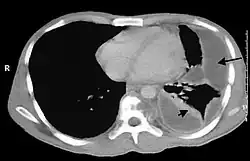

Bei der körperlichen Untersuchung sind ein abgeschwächtes Atemgeräusch bei der Auskultation und ein gedämpfter (hyposonorer) Klopfschall bei der Perkussion über dem Pleuraempyem typisch aber unspezifisch. Für die Diagnose von Pleuraempyemen reicht meist eine konventionelle Röntgenaufnahme des Brustkorbs. Pleuraempyeme sind hier durch eine deutliche Transparenzabnahme gekennzeichnet. Die Eiteransammlung zeigt sich im Röntgenbild in Form einer Spiegelbildung. Bei unklaren Befunden kann eine Computertomographie des Brustkorbs angefertigt werden.